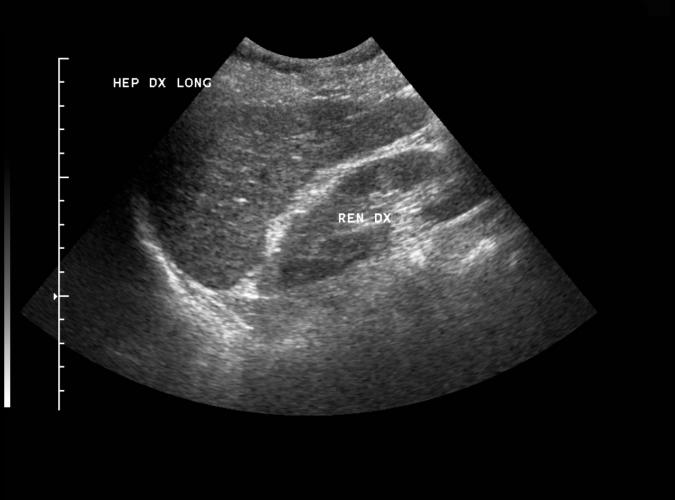

Patologi.

Long. Lågekogen, skrumpen höger leverlob med oregelbundna kanter. Bild som tillsammans med bild 3a,b,c,d talar för

biliär cirrhos